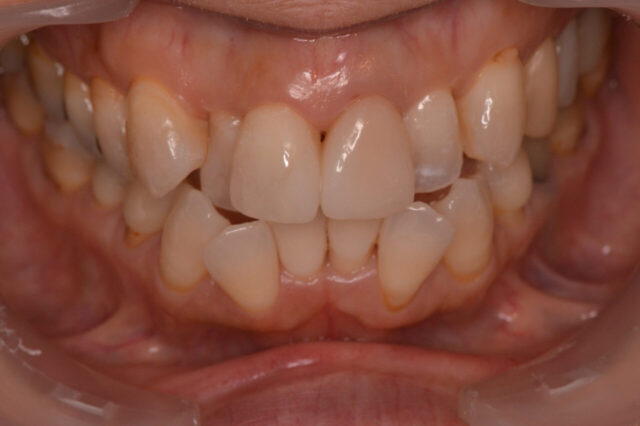

性別 女性 主訴 「前歯の色が気になる」「できれば削らずにきれいにしたい」というご相談で来院されました。 治療 診査の結果、前歯には失活歯による内部からの変色(いわゆる黒ずみ)が認められました。

通常であれば、ラミネートベニアやセラミッククラウンによる修復が検討されるケースです。

しかし本症例では、歯質の保存を最優先に考え、以下の治療を選択しました。

インターナルブリーチ(ウォーキングブリーチ)による内部漂白

色調改善後にダイレクトボンディングによる形態・色調修正

まず歯の内部に漂白剤を作用させることで、歯質自体の明度を改善。

その後、周囲の歯との色調バランスを考慮しながらコンポジットレジンにて微調整を行いました。

結果として、歯を大きく削ることなく、自然で調和のとれた前歯の審美性を回復することができました。料金 1本10万円+tax 備考 本症例のポイントは、「削らない選択肢」を最大限活かした点にあります。